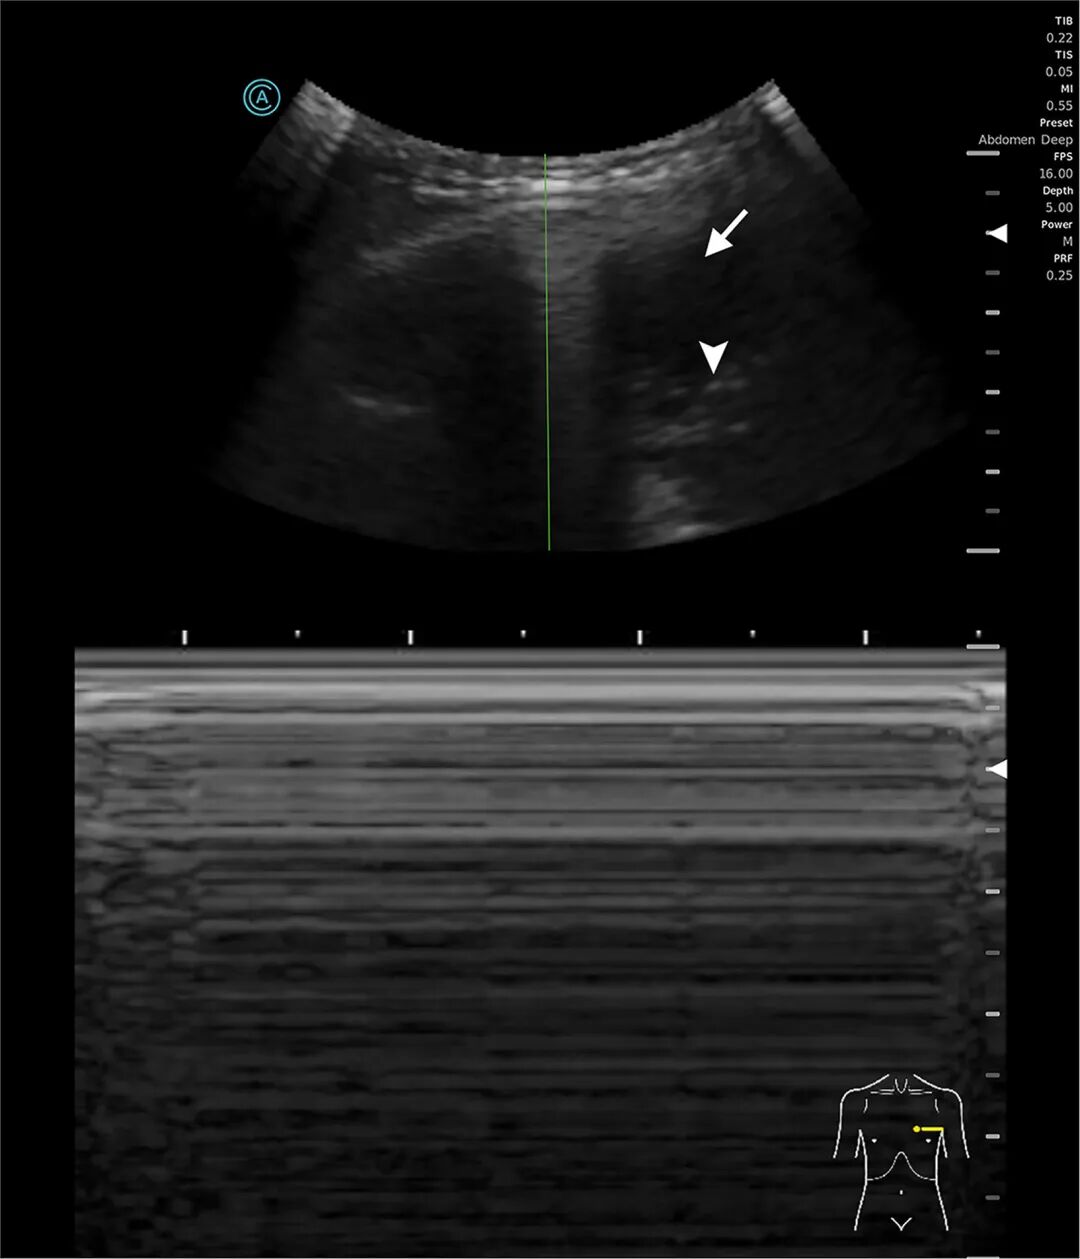

行床旁超声(图1)显示左侧大量胸腔积液,可见浮游物,且肺滑动征消失。计算机断层扫描(CT)证实左侧广泛脓气胸伴纵隔移位(图2)。

图1:左侧胸廓M型超声

图1超声显示气胸时平流层征(条形码征)。由于肺滑动征消失,M型超声图像全程表现为均匀的水平线(正常沙滩征模式消失)。胸膜线显示为清晰的高回声水平线。在B型图像右侧可见低回声胸腔积液(箭头)及游离气体(三角箭头),符合脓气胸表现。肺滑动征消失同时合并可见胸腔积液提示复杂胸膜病变。图2显示左侧大量胸腔积液,并可见气液平面(三角箭头),提示胸膜腔内存在游离气体。非重力依赖性游离气体(箭头)在积液最上方形成清晰、光滑的气液界面,符合液气胸(胸腔积液合并气体蓄积)表现。塌陷的左肺向上受压(星号)。上述表现符合脓气胸伴大量胸腔积液。

超声可见胸腔积液伴浮游物征且肺滑动征消失,提示脓胸。厌氧菌产生的气体可解释气胸的形成。